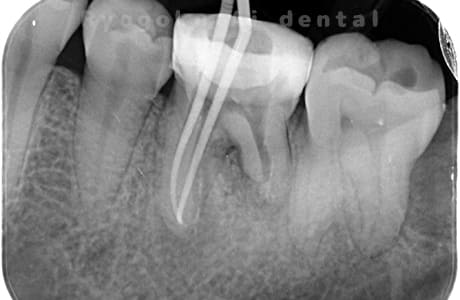

Case04

-

- 原因

- 慢性根尖性歯周炎

- 治療期間

- 3ヶ月

- 治療内容

- マイクロエンド

- 治療費用

- 121,000円

噛むと痛みが出る、とのことで来院した患者様です。他院での根管治療を終えてましたが、根尖病変を認めるため、マイクロエンドを行いました。